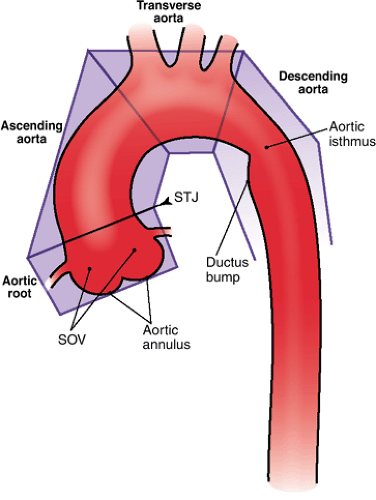

Нормальный диаметр корня аорты: медицинские нормы и отклонения